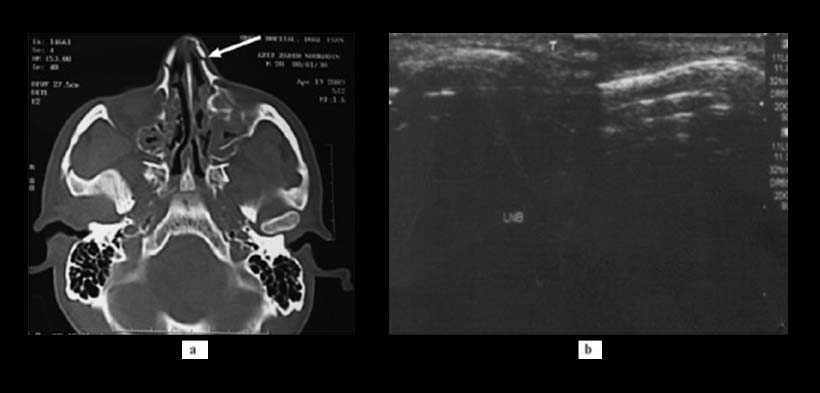

Fig. 3. Un hombre de 25 años de edad con una fractura de hueso nasal izquierda (flecha blanca). (a) Vista CT y (b) sonograma que no mostró la fractura del hueso nasal izquierdo.